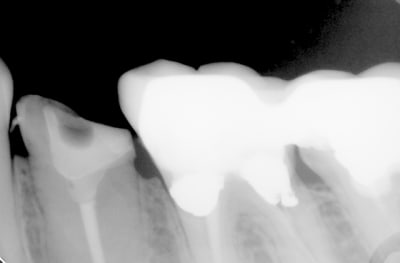

Voilà ce patient a consulté en Juillet pour une douleur à la mastication. Je regarde la radio, belle pêche sous les racines, en bouche, une fêlure traversant la dent dans le sens MD. A votre avis que faire dans ces cas et comment évaluez vous la réussite ou non de l'endo - CCC dans ces cas? Il n'avait aucune douleur quand j'appuyais transversalement de sur la moitié linguale ni sur la moitié vestibulaire (vers l'extérieur de la dent, pour "séparer" les dent).

Bref je fais l'endo, et lisant de plus en plus de choses sur le sans-tenon (surtout le risque de fracture supérieur qu'il engendrait par perte de substance dentinaire) je me suis lancé dans un "Nayyar" core, compo descendant dans les entrées canalaires et par dessus une CCC.

Ci-joint les radios.